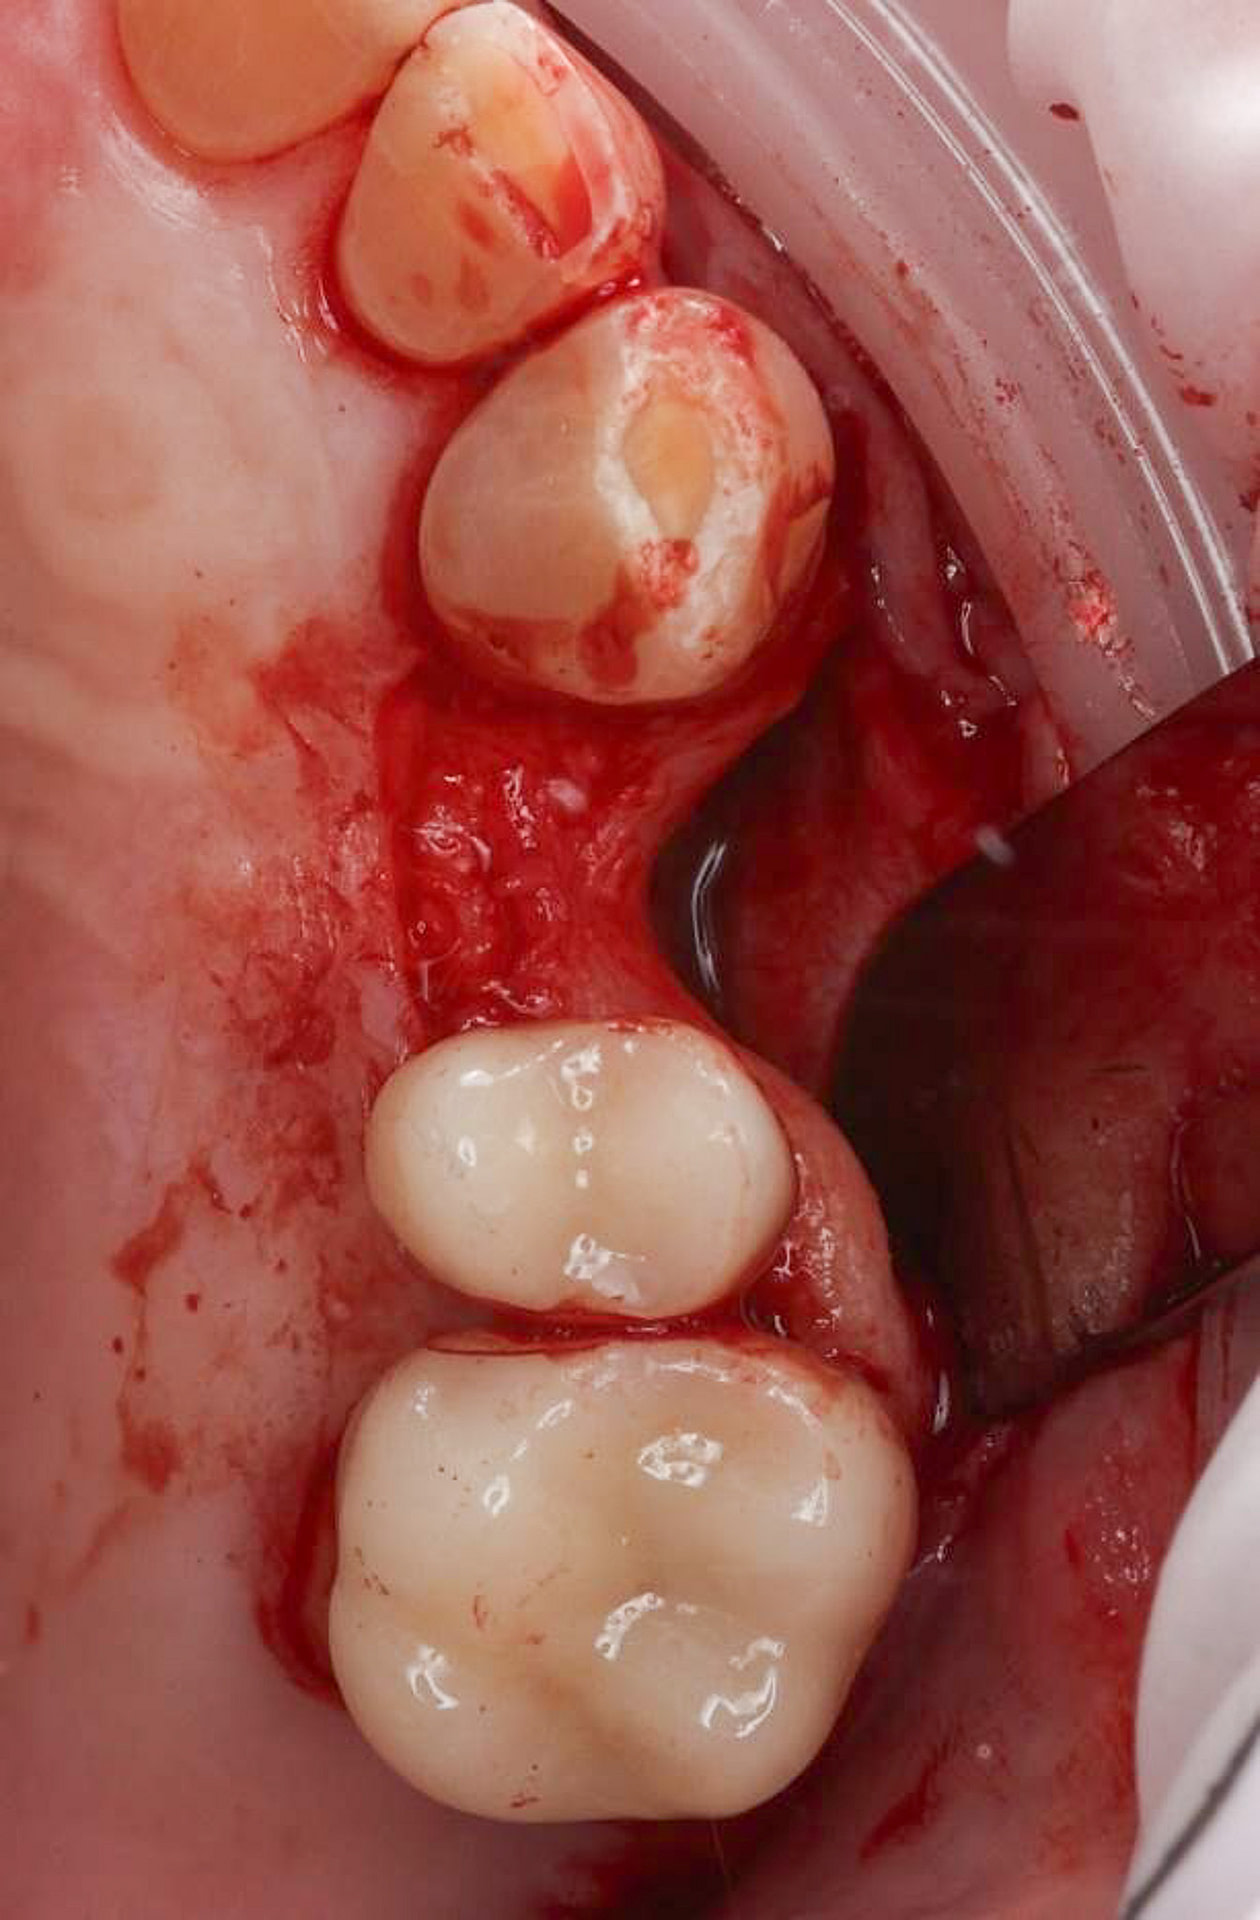

Upon examination by his previous dentist, a vertical root fracture was diagnosed, necessitating a surgical extraction. The procedure, which involved removing the buccal cortical bone, left the patient with a bony defect in the area of the extracted tooth.

The treatment plan consisted of crowning teeth 25 and 26, replacing missing tooth 24 with a dental implant, and placing a bone graft to replace lost bone tissue and provide a stable foundation for the implant.

The surgical phase of the implant treatment is a critical step in ensuring the success and longevity of the final restoration.

A custom surgical guide was designed and 3D printed, incorporating all the critical information from the virtual planning. The implant surgery was performed under local anesthesia, with the surgical guide firmly in place to ensure accurate implant placement. Bone grafting was performed to address the bony defect and promote optimal healing.

The Osstem OneGuide kit is used with a fully guided osteotomy and implant placement.

Osstem TSIII D4 x H10mm implant on NoMount driver.